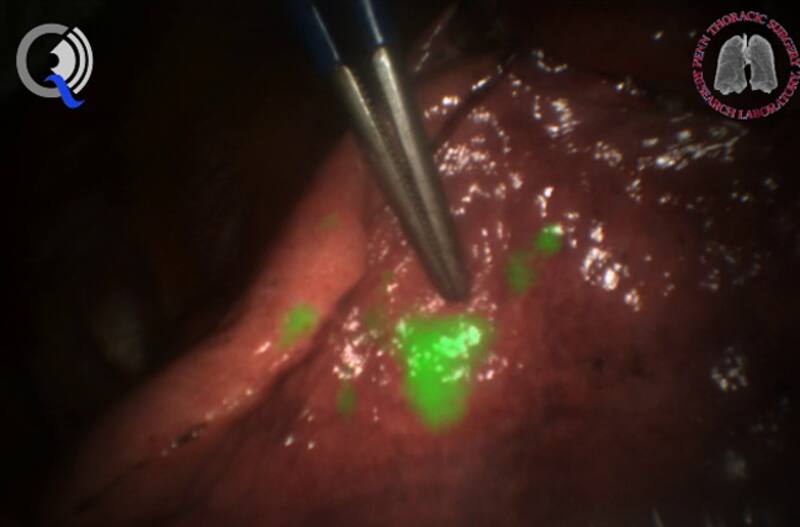

2. Tumores brillantes

TumorGlow, una tecnología de imágenes registrada por Penn, utiliza un tinte inyectado para ayudar a los médicos a ver los tumores con mayor claridad durante la cirugía. A los pacientes se les inyecta un tinte que ha sido diseñado para adherirse a las células cancerosas. Durante la cirugía, los médicos utilizan cámaras infrarrojas bajo las cuales el tinte brilla. Los cirujanos pueden ver más claramente dónde está el tumor y estar más seguros de haberlo extirpado por completo.

La tecnología ya fue aprobada por la Administración de Alimentos y Medicamentos de EE.UU. (FDA, su sigla en inglés) para su uso en el tratamiento del cáncer de ovario y pulmón. “Representa la primera vez en mucho tiempo que ofrecemos a nuestros cirujanos una nueva herramienta”, dijo Vonderheide.